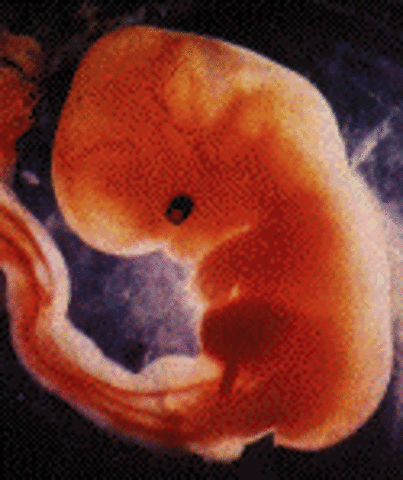

• week 5 Begginning of Embryonic stage

week 5 Begginning of Embryonic stage

cells of the ovum start making the amniotic sac, and placenta. other cells will begin to begin forming the embryo itself. embryo wil double in size by the end of the week. The embryo grows to 5mm

Fact: nerve and spinal chord begin early stages of development.